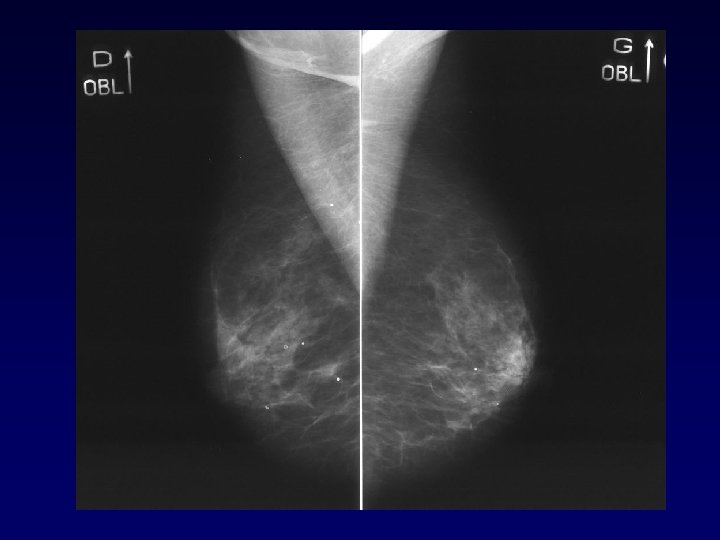

Analyse faux-négatif • • • Corrélation avec analyse de pièces de mastectomies coupées en 5 mm 99 seins (188 K) IRM : Sen = 81 % (89 % KI, 40 % KIS) MM : Sen = 66 % (72 % KI, 37 % KIS) F- : IRM : 5, 6 mm, MM : 10, 9 mm Performance = sein densité BIRAD 1 AJR Sardanelli 2005

Analyse Faux négatif K invasif 28 cas (Teifke adiology 2002) • Technique : 5 cas • Rehaussement masquant : 3 cas • Caractéristiques histologiques : 5 cas • Taille : 15 cas : ≤ 5 mm

Performance de l’IRM pour le diagnostic de CCIS • Peu de résultats – Non indication de l’IRM (mammographie / microcalcifications) – IRM plus performante pour diagnostic de CCIS de haut grade que de bas grade – Potentiel dans le bilan d’extension • Les CCIS représente un taux important des cancers biopsiées sous IRM (> taux des cancers découverts par IRM) (64 CCIS pour 74 K invasif dans la série multicentrique européenne – Cancer 2006)